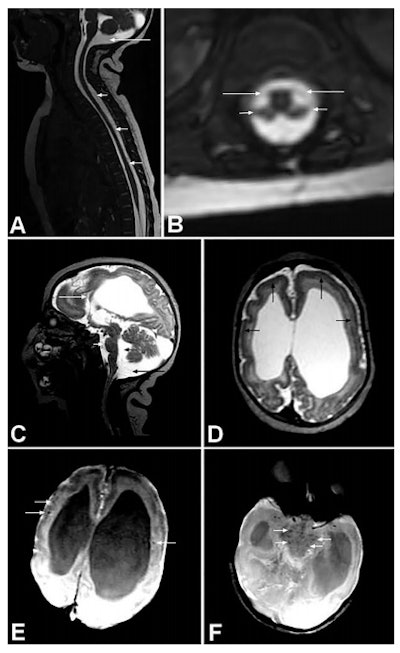

The seven children underwent neurological and orthopedic examinations along with several other investigations: radiography, brain CT, or brain MRI without contrast, high-definition ultrasound of the joints (with specific attention to cartilage, synovia, pericapsular structures, and muscular tissue around joints), nerve conduction studies, and needle electromyography. If calcifications were present on brain imaging (CT or MRI), the researchers considered the possibility of congenital infections. Four children underwent MRI of the spine. MRI was not possible in two children as they were receiving mechanical ventilation on an intensive unit care.

All children showed signs of brain calcification. The theory is the Zika virus destroys brain cells, and forms lesions on which calcium is deposited. There was no evidence of joint abnormalities. This led van der Linden et al to note the arthrogryposis did not result from abnormalities of the joints themselves, but was likely to be of neurogenic origin, leading to fixed postures in the womb and consequently deformities.